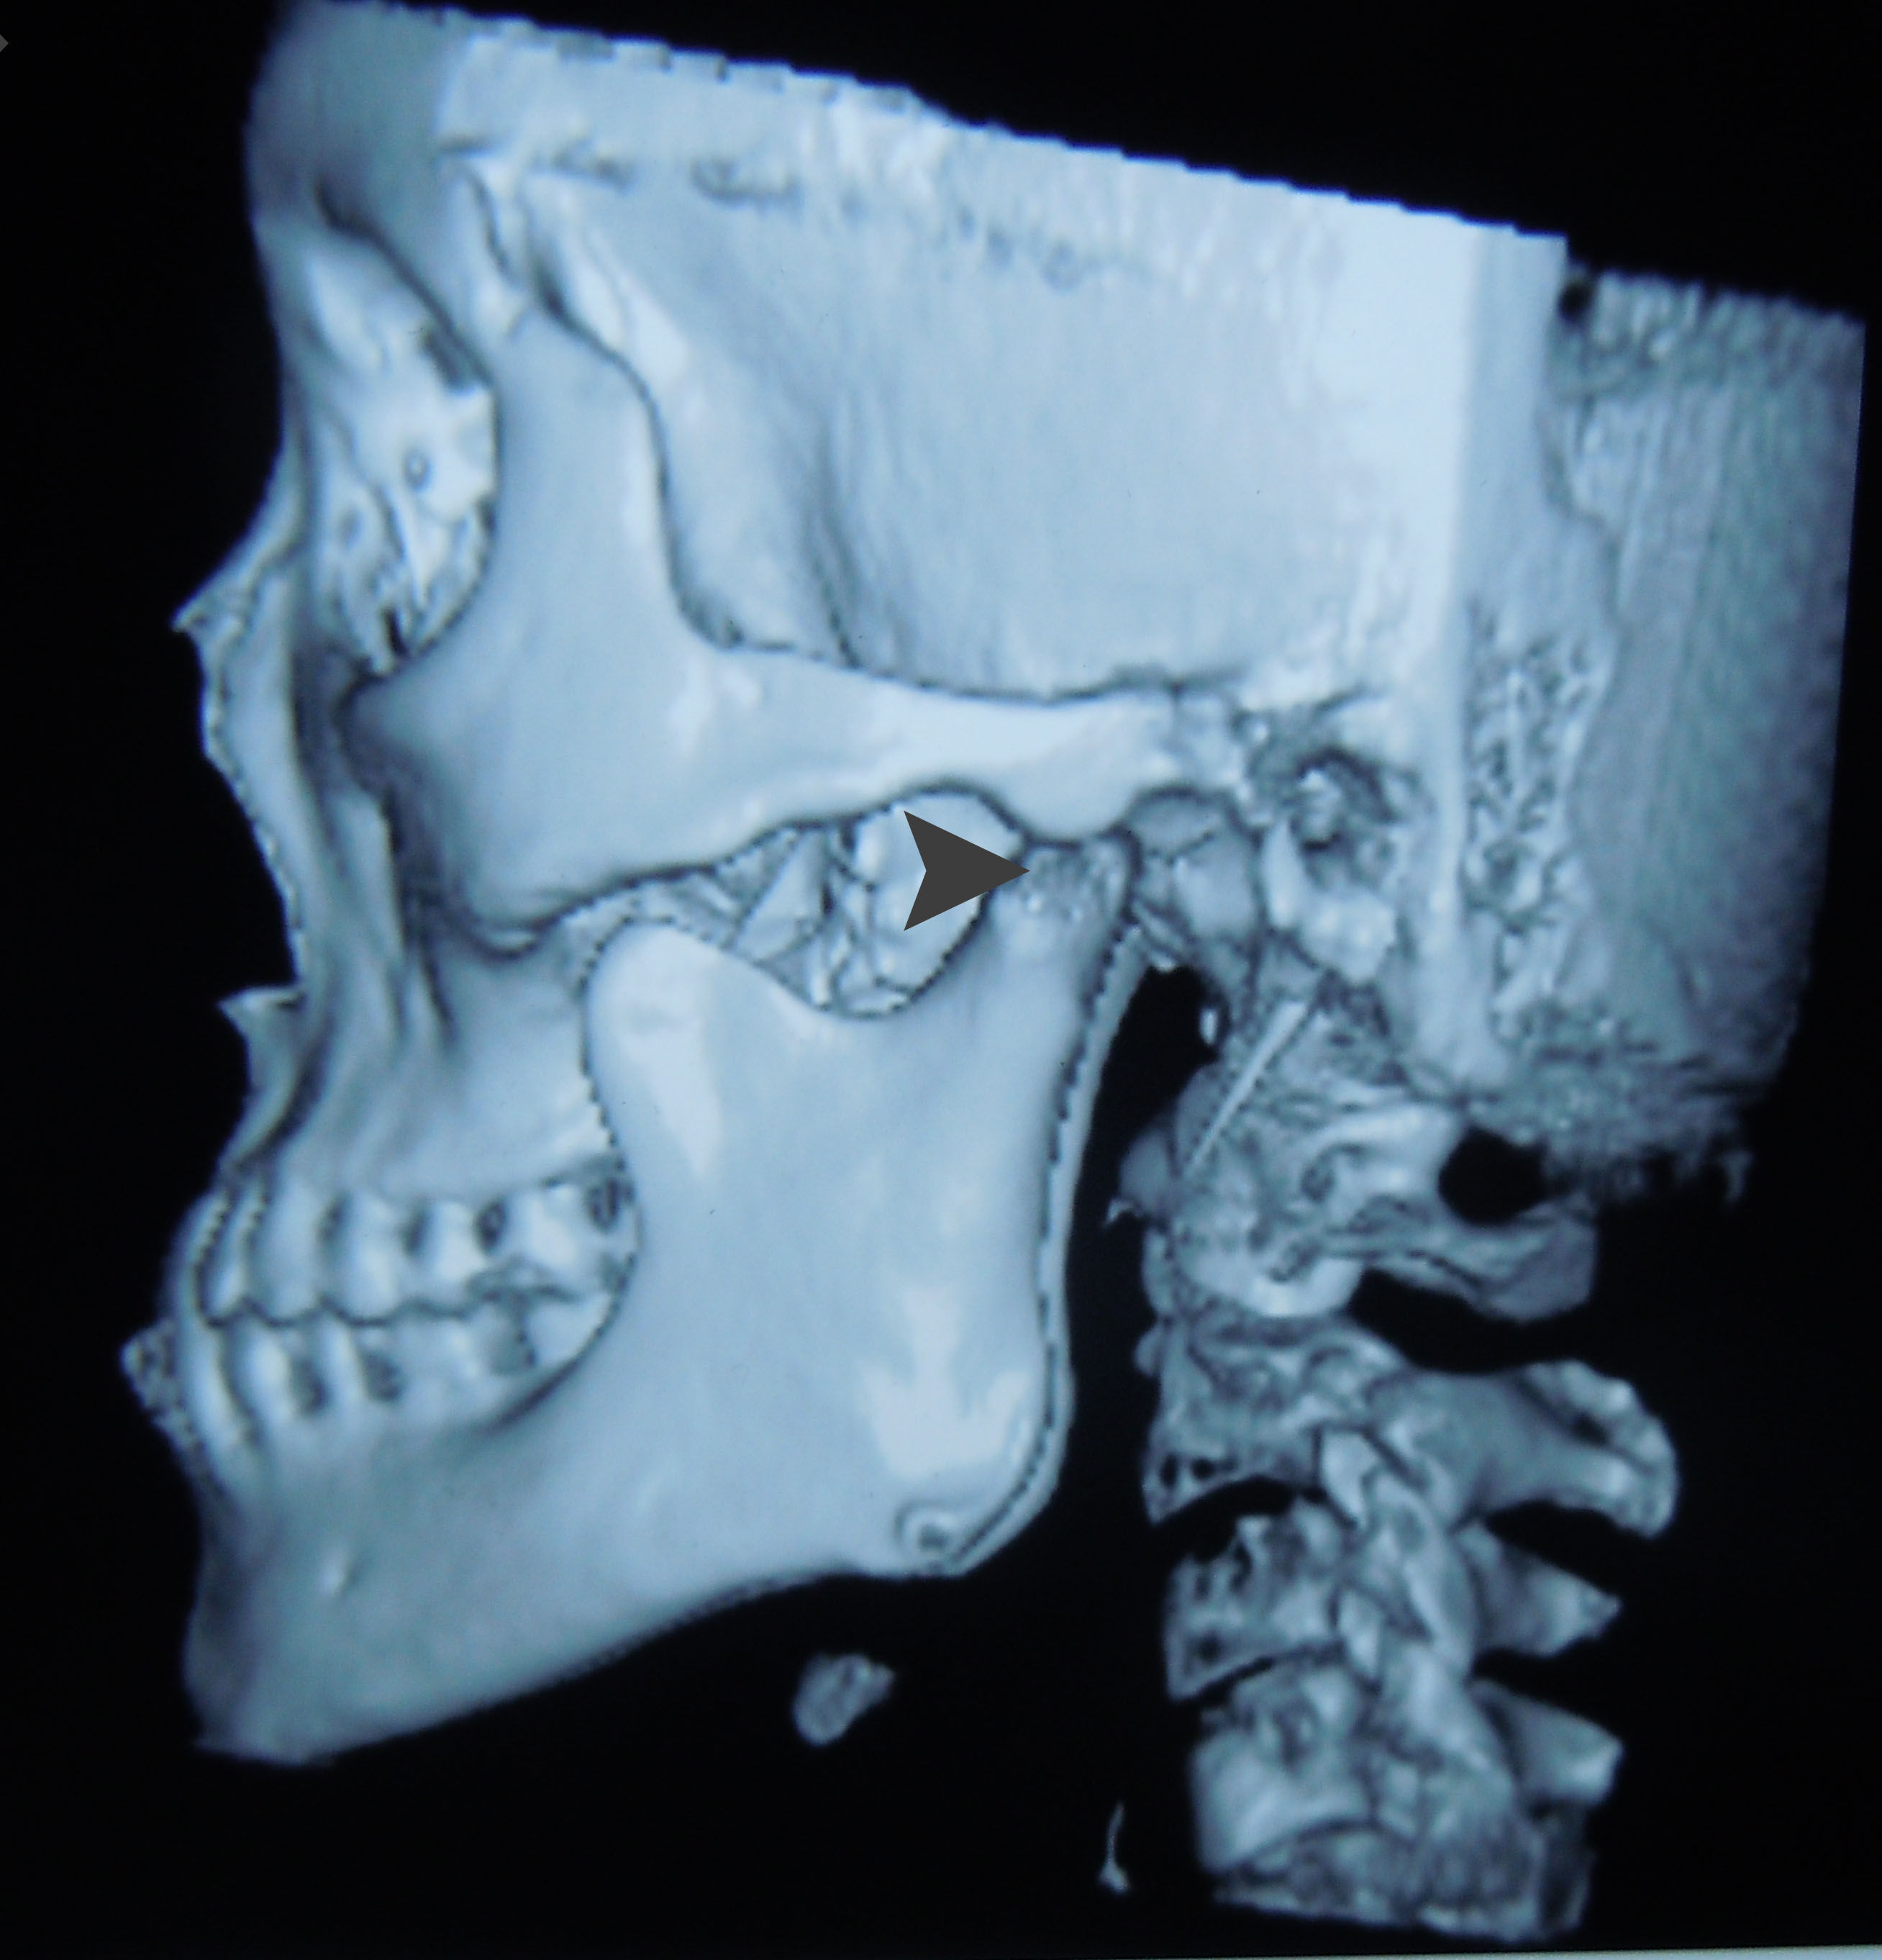

一年前患者突然出现面部偏斜,于南京就诊,南京医生说是一侧颞下颌关节的过度发育,等患者关节没有发育完成,不能手术,没能诊断出关节脱臼,这是脱臼当时的磁共振片子,片子显示颞下颌关节髁突(arrow head)明显脱离了关节窝(arrow)

来我院就诊时左侧关节窝空虚,前牙反颌,偏斜

颞下颌关节的髁突脱离了关节窝,卡在关节结节的前面一年,在脱臼的早期是非常疼痛的,不能合拢嘴巴,前牙咬不上。可是这个病人现在一点都不疼,牙齿能错位的咬合上,看见当初这个病人当初忍受的多少天的痛苦呀。做为医生不能想像。

要求拍CT,ct显示左侧髁突骨质改建良好,可以考虑正畸治疗这种反颌,后来我们考虑这个人都27岁了,对面容要求也不高了,而且牵引钉拉髁突向后的力量不足,是因为上下颌牙尖的锁结很厉害,所以建议戴薄稳定合垫,打开咬合,同时戴颏兜加大向后的力量,再观察一个月。